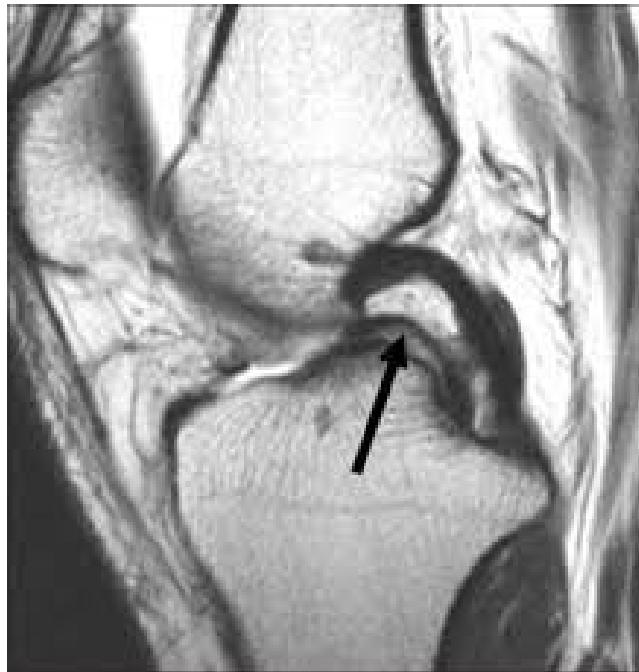

| ACL & PCL: Anterior/Posterior Drawer Test OR Lachman’s test OR Pivot Shift test | Assess integrity of Anterior and Posterior Cruciate Ligaments specifically | Anterior/Posterior Drawer Test: Lachman’s test: ![]() | Excessive anterior or posterior translation of the tibia, indicating ACL or PCL injury | |

| PCL: Drawer test OR posterior Sag test | Specifically assess Posterior Cruciate Ligament integrity | Sagging sign: ![]() | Posterior sagging of the tibia when the knee is flexed, indicating PCL tear | |